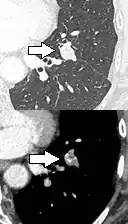

Part solid nodule.[9]

Part solid nodule.[9] Ground glass opacity nodule.[9]

Ground glass opacity nodule.[9]